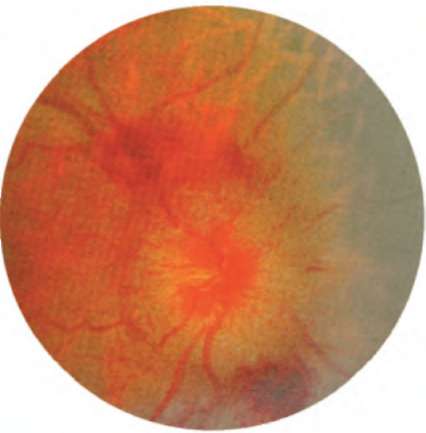

Рис. 12.3. Осложненный застойный диск зрительного нерва. Его гиперемия, отек и выстояние в стекловидное тело. Вены сетчатки расширены, извиты, мелкие штриховые кровоизлияния по краям. Крупные преретинальные и ретинальные кровоизлияния